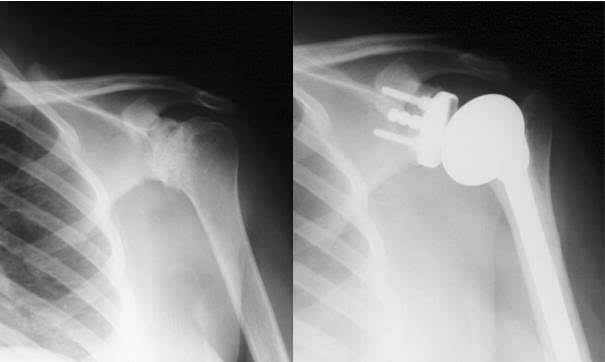

因為肱骨頭較大,呈球形,關(guān)節(jié)盂淺而小,肩關(guān)節(jié)僅包繞肱骨頭的1/3,關(guān)節(jié)囊薄而松弛,所以肩關(guān)節(jié)是人體運動范圍最大而又最靈活的關(guān)節(jié),它可做前屈、后伸、內(nèi)收、外展、內(nèi)旋、外肩關(guān)節(jié)是由肩胛骨的關(guān)節(jié)盂與肱骨頭組成,故又叫肩肱關(guān)節(jié)。 因為肱骨頭較大,呈球形,關(guān)節(jié)盂淺而小,僅包繞肱骨頭的1/3,關(guān)節(jié)囊薄而松弛,所以肩關(guān)節(jié)是人體運動范圍最大而又最靈活的關(guān)節(jié),它可做前屈、后伸、內(nèi)收、外展、內(nèi)旋、外旋以及環(huán)轉(zhuǎn)等運動。

但肩關(guān)節(jié)的這個結(jié)構(gòu)上的特點雖然保證了它的靈活性,但它的牢固穩(wěn)定性都較其他關(guān)節(jié)為差,是全身大關(guān)節(jié)中結(jié)構(gòu)最不穩(wěn)固的關(guān)節(jié)。 最常見的是向肩關(guān)節(jié)的前下脫位,因為肩關(guān)節(jié)的上方有肩峰、喙突及連于其間的喙肩韌帶,可以防止肱骨頭向上脫位。

肩關(guān)節(jié)的前、后、上部都有肌肉、肌腱與關(guān)節(jié)囊纖維層愈合,增強了其牢固性。而只有關(guān)節(jié)囊的前下部沒有肌肉、肌腱的增強,這是肩關(guān)節(jié)的一個薄弱區(qū)。

因此當上肢外展時,在外力作用下或跌倒時,如上肢外展外旋后伸著地,肱骨頭可沖破關(guān)節(jié)囊前下方的薄弱區(qū),移出到肩胛骨的前方,造成肩關(guān)節(jié)前脫位。 這時患肩塌陷,失去圓形隆起的輪廓,形成所謂的“方肩”。